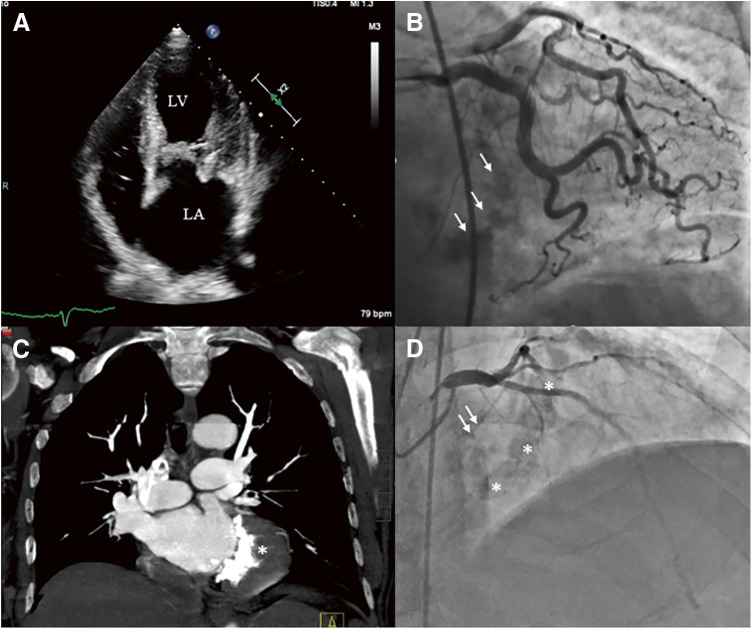

二尖瓣环钙化增加了二尖瓣置换术(MVR)的复杂性。标准程序要求在放置假体之前进行脱钙,然后重建二尖瓣环。虽然这是一种理想的技术,但由于相关的风险,并不是对每个病人都可行。单纯尝试瓣膜置换术而不进行适当的环脱钙会导致假体周围泄漏的高发生率,这使术后过程复杂化,并增加了发病率和死亡率。随着经导管治疗的进步,术后假体周围的反流可以用器械控制,经导管瓣膜植入术可以替代标准的瓣膜置换术;然而,这些替代策略并非没有其自身的局限性和缺点。在目前的报告中,我们提出了一种新的策略,用于一组有严重但非环性钙化的患者,以预防/减少MVR期间假体周围的反流。这包括在位于后方的钙棒上放置一个贴片,从而最大限度地减少后缝合线的张力,并控制任何假体周围的反流。这种修改已在总共9例病例中进行,早期结果可接受。

Mitral annular calcifications have been known to increase complexity during mitral valve replacement (MVR). Standard procedure requires decalcification followed by reconstruction of the mitral annulus prior to placing the prosthesis. While this is the ideal technique, it is not feasible in every patient due to the associated risks. The mere attempt at valve replacement without proper annular decalcification has been associated with a high incidence of periprosthetic leak which complicates the postoperative course and has been associated with increased morbidity and mortality. With the advances in transcatheter therapy, postoperative periprosthetic regurgitation can be managed with devices and primary transcatheter valve implantation could be alternative to standard valve replacement; however, these alternate strategies are not without its own limitations and drawbacks. In the current report, we present a novel strategy to be used in a select group of patients with severe but non-circumferential annular calcifications to prevent/minimize periprosthetic regurgitation during MVR. This involves placing a patch over the posteriorly located calcium bar, thus minimizing tension on the posterior suture line and contain any periprosthetic regurgitation if to develop. This modification has been performed in a total of nine cases with acceptable early results.